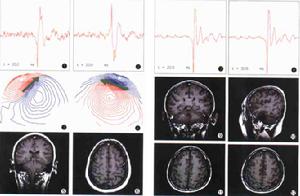

按照被檢測者的分類有:腦腫瘤,癲癇,頭部輕度外傷,腦中風后遺症,精神分裂症、痴呆症等。其中至少在4個臨

1969年,Cohen第一次成功地利用超導量子干涉儀(superconductingquantuminterfereddevice,SQUID)檢測到顱內電流變化產生的磁場,奠定了腦磁圖的基礎,成為腦磁圖研究的核心理論,使MEG的探測水平發生了一個質的飛躍,具備了現代腦磁圖技術的雛形。